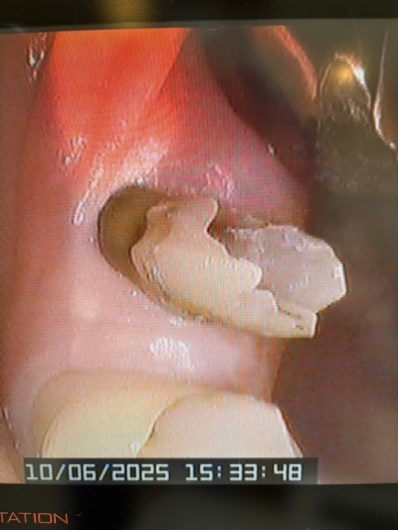

ファイバーポストによる歯根の土台補強

根管治療後、補強のための土台作り。

ファイバーポストは歯の柔らかさに近いしなりを持ち尚且つ接着剤が歯に染み込んで固まるので歯との一体感が抜群です。そのため長期に渡り歯根を守る役割を果たしてくれる強い味方なんです。